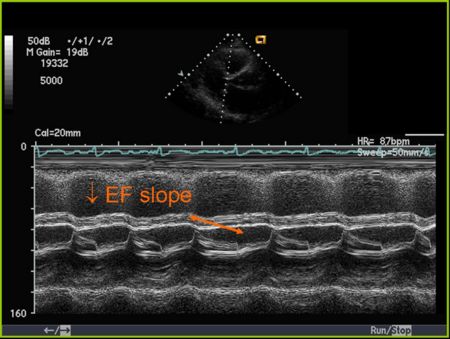

Mitral Valve M-mode Analysis

- Anterior leaflet with E/A appearance of diastology

- Decreased EF slope in MS

M Mode in Mitral Stenosis

- Leaflet tips bright (calcified) and thickened

- E/F slope decreased